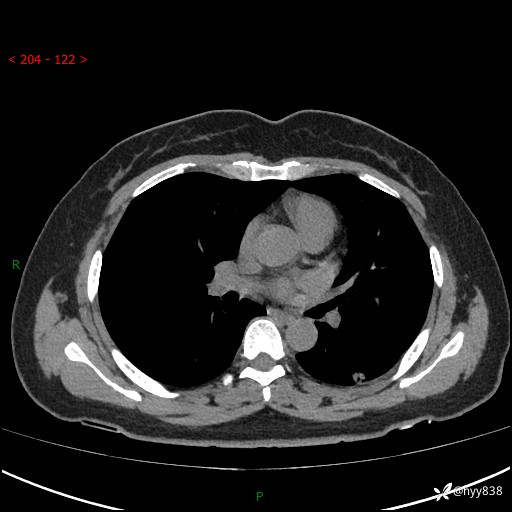

现病史:患者1年前因“咳嗽”就诊于我院门诊,查胸部CT提示:左肺结节,建议患者3月后复查,患者遂于2023-07-28再次于我院门诊查胸部CT,提示同前,建议患者1年后复查,现患者为求复查,再次来院,查胸部CT示:左下肺部分实性结节,较前(2023.7.28)体积稍大,现患者偶有咳嗽、咳痰,多为白痰,3天前患者出现痰中带血,为鲜血,2天前停止咯血,现患者为求进一步诊治,就诊于我院门诊,现以“孤立性肺结节”收住我科。 起病来,患者精神、食欲、睡眠尚可,体力、体重无明显变化。

胸部CT复查+增强(2024.6)